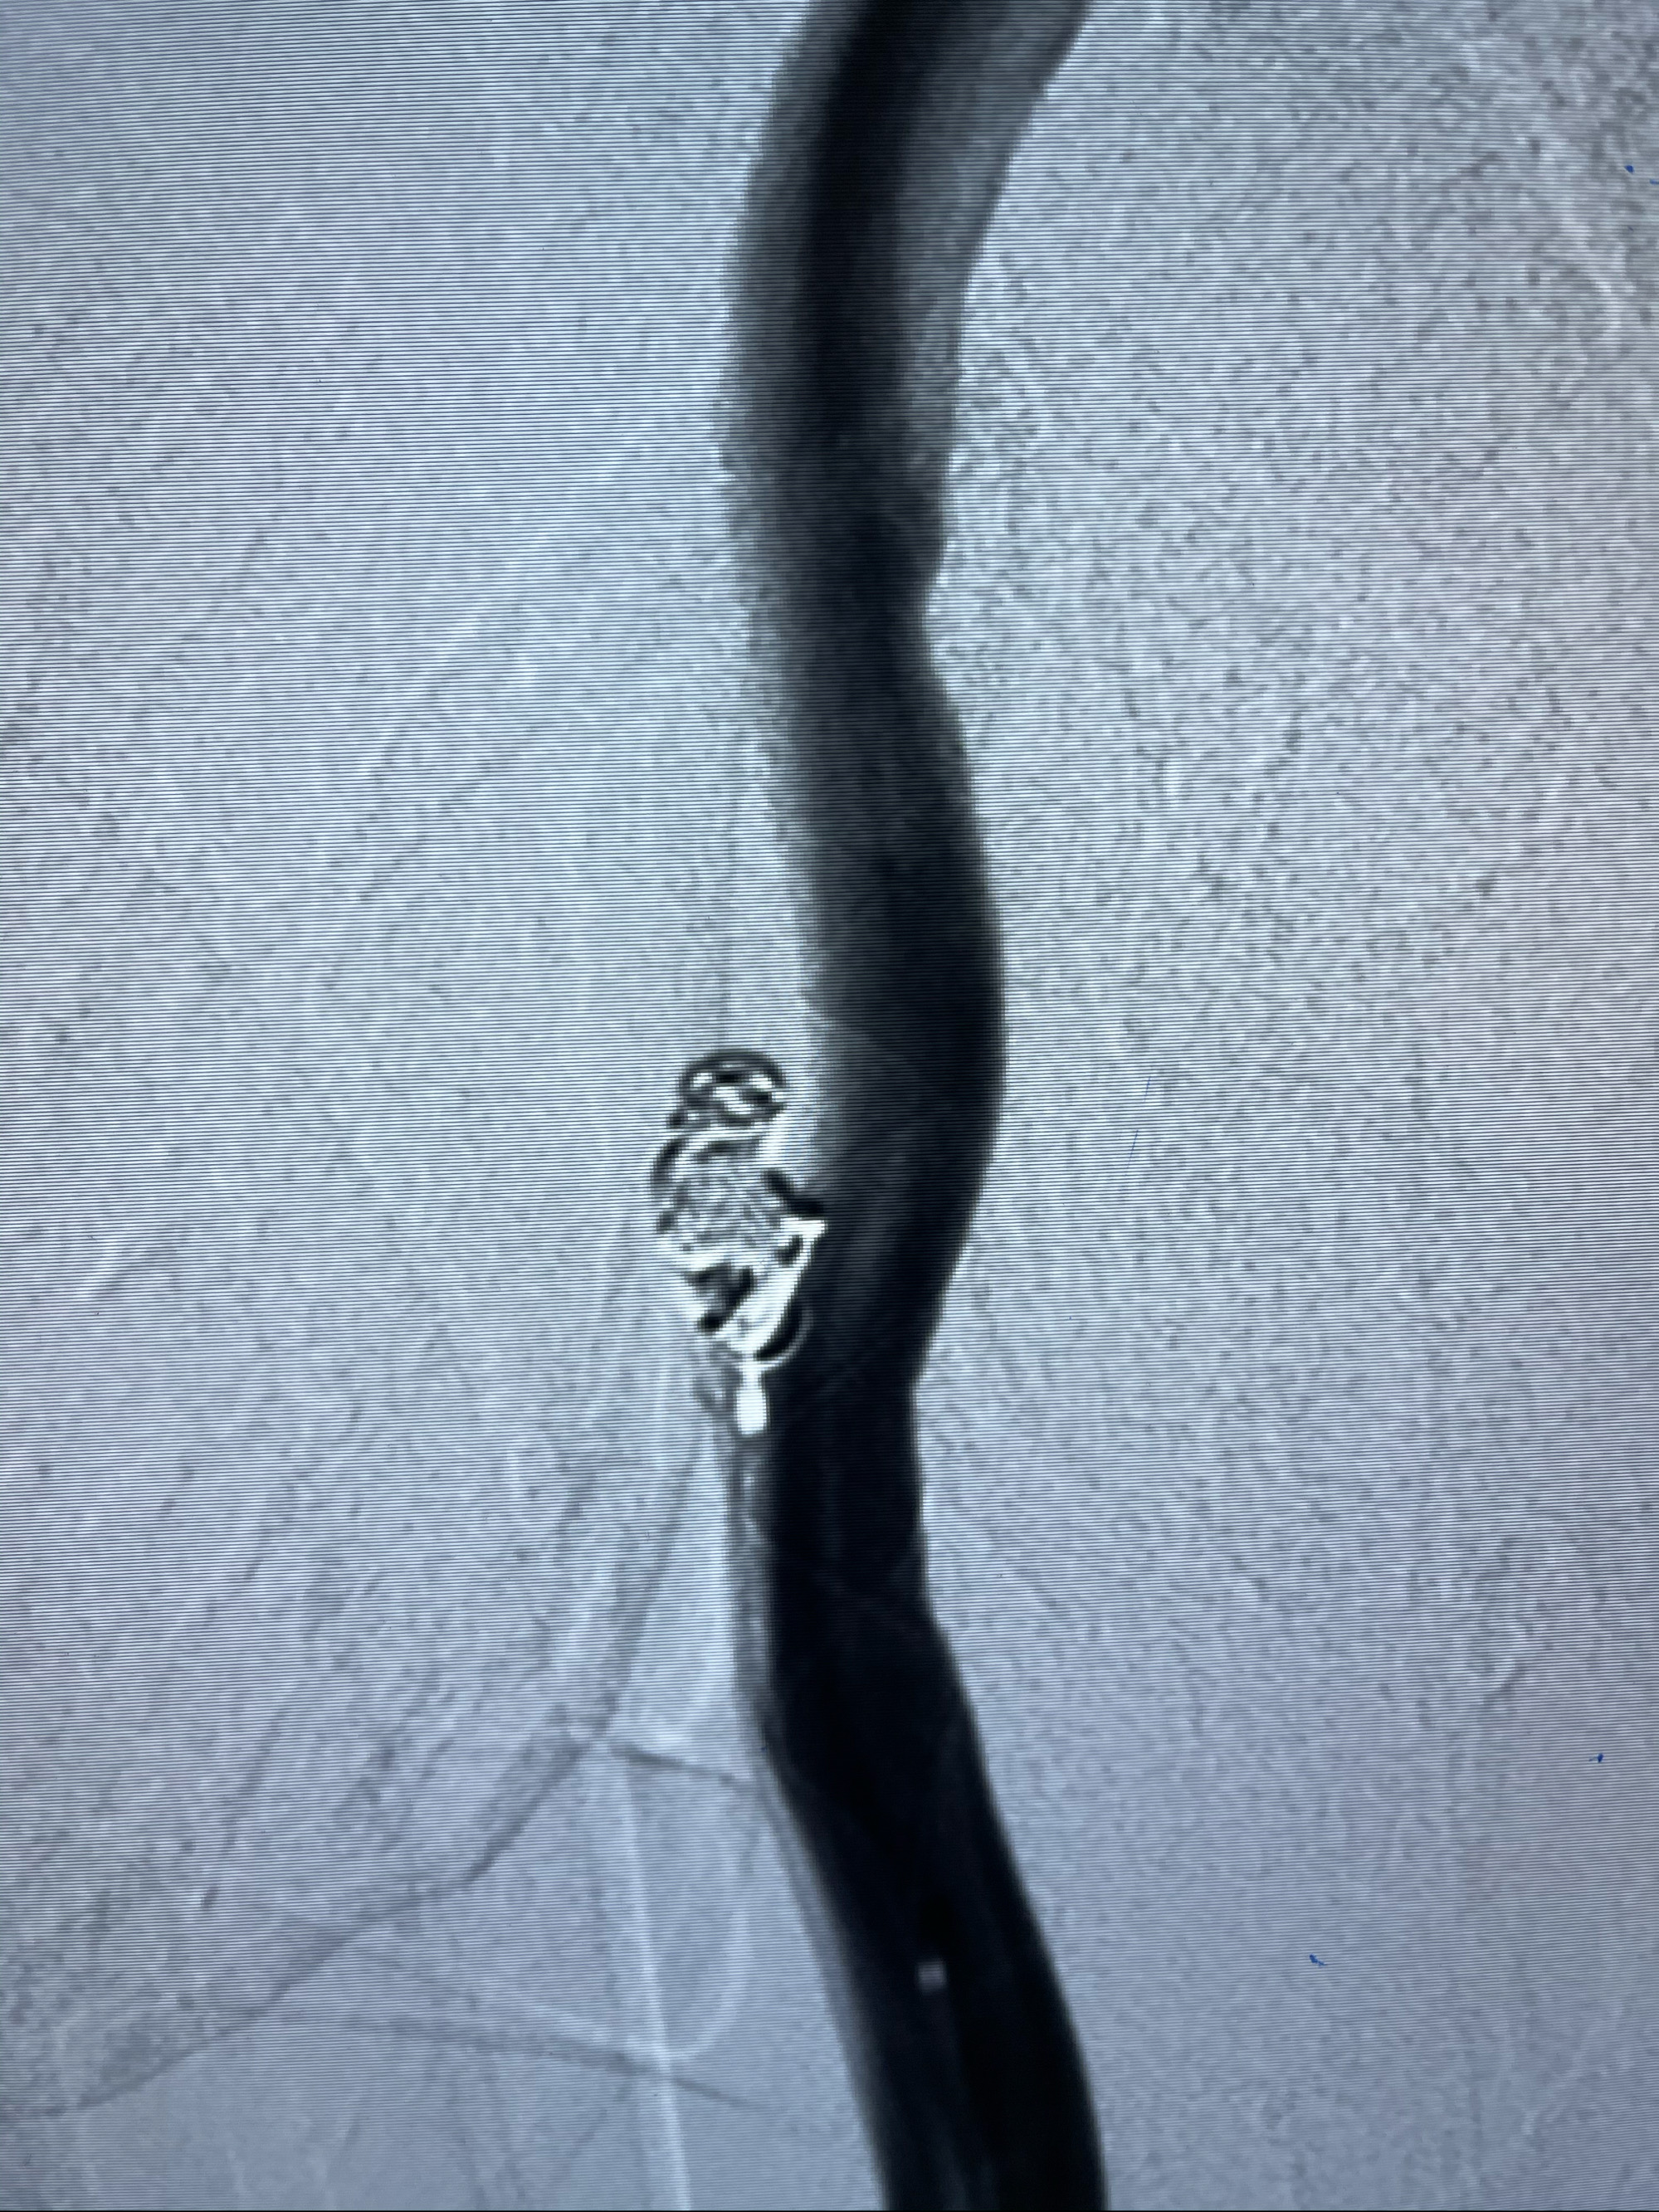

工作角度造影

即刻造影